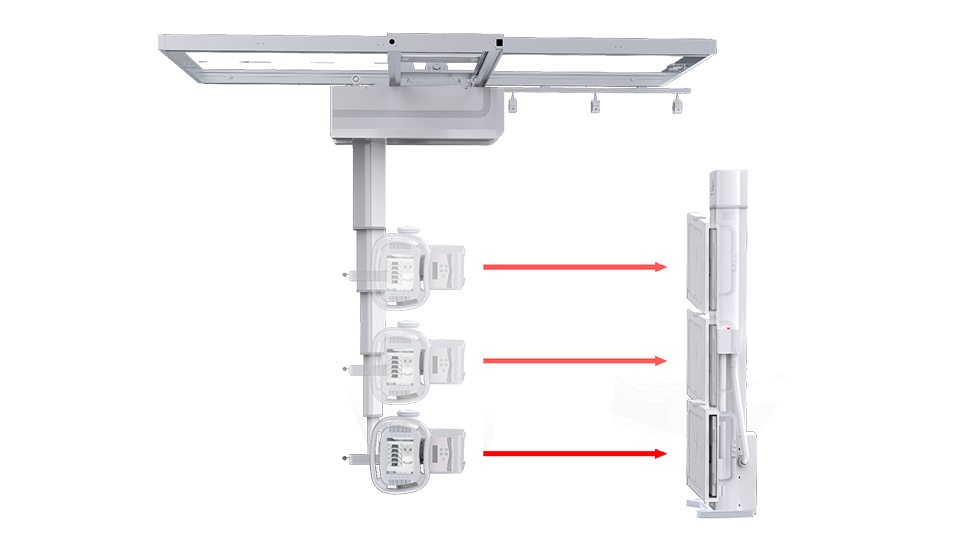

● 自动跟踪

配备球管与平板联动控制系统,平板端上下移动时,球管端自动跟踪。

● 拍摄无死角

悬吊运动范围大,牛头可全角度旋转,倾斜投照位可满足特殊病人的临床应用。